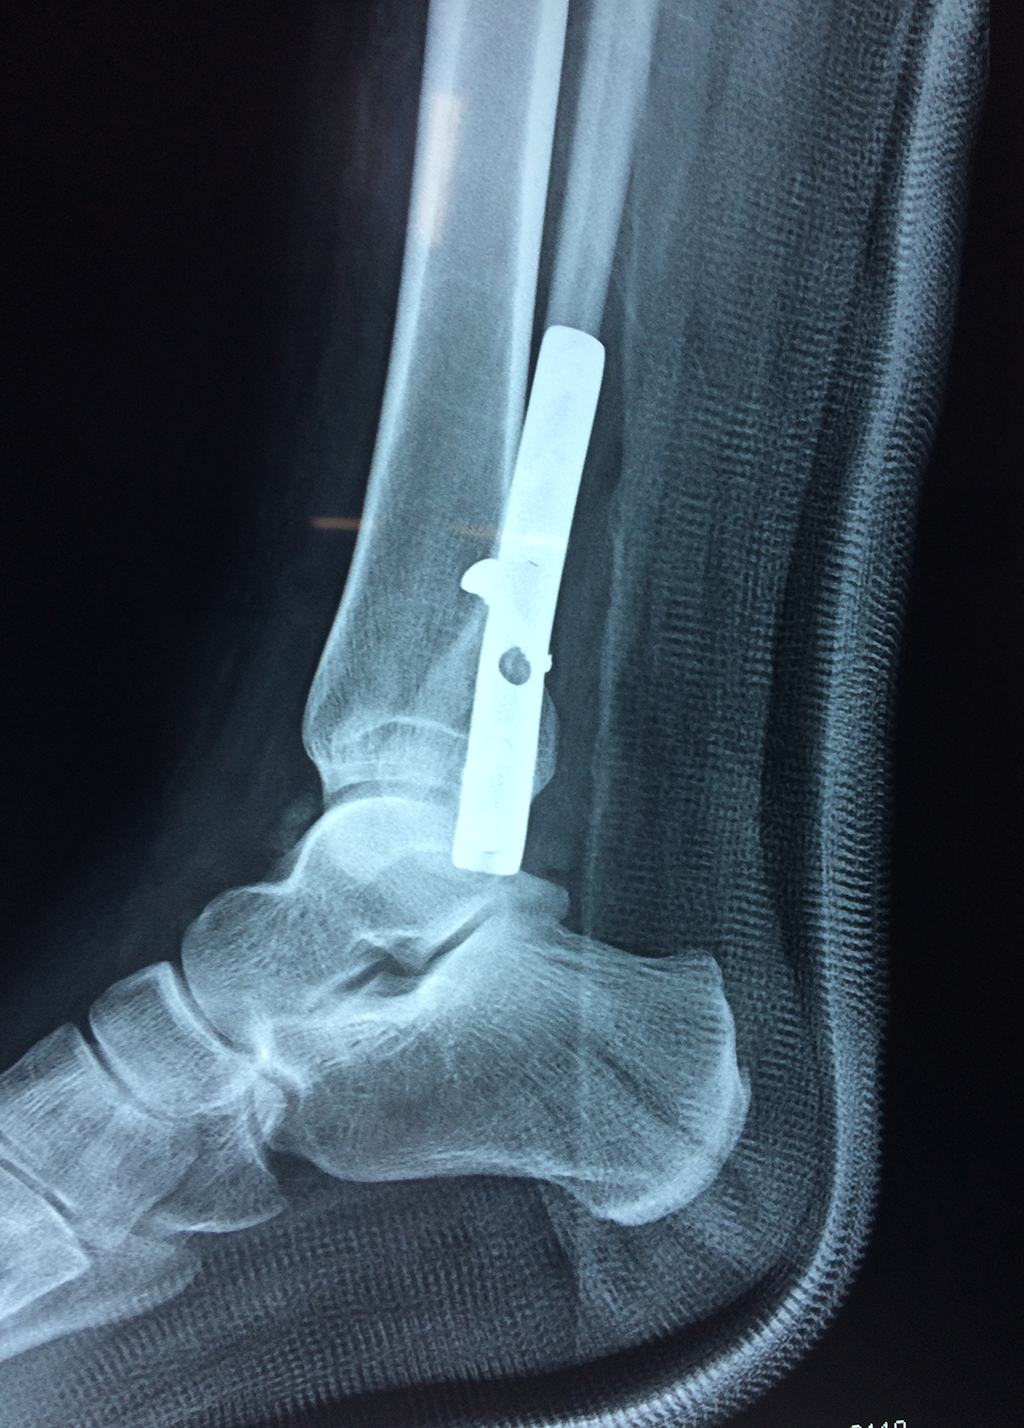

Cuando se necesita cirugía, es probable que esta implique el uso de clavijas de metal, tornillos o placas para sostener los huesos en su lugar mientras la fractura se consolida. Los elementos de soporte pueden ser temporales o permanentes.

Algunas fracturas de tobillo pueden requerir cirugía si:

- Los extremos de los huesos están desalineados entre sí (desplazados).

- La fractura se extiende hasta la articulación del tobillo (fractura intra-articular).